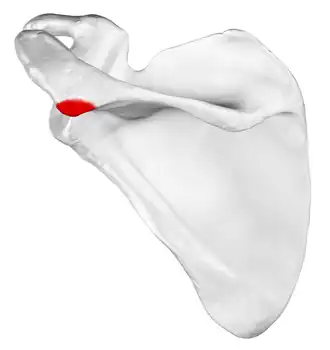

![]() Left scapula, posterior view. Acromion shown in red. | |

Left scapula. Acromion shown in red. -